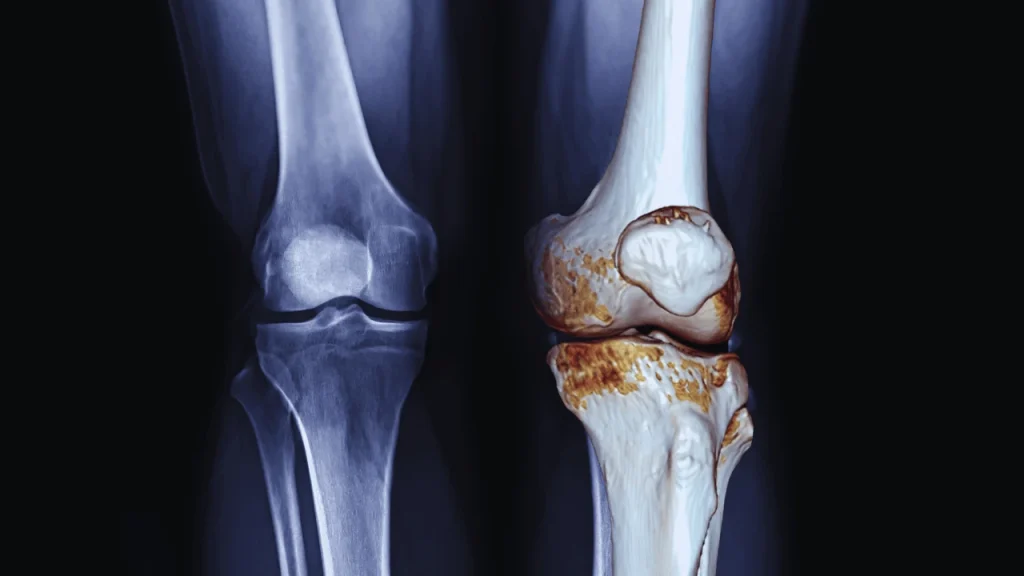

How Barometric Pressure Affects Joint Pain

How Weather Changes and Barometric Pressure Affect Joint Pain — And How Physiotherapy in Burnaby Can Help Have you ever heard someone say, “I can feel the rain in my knees”? As odd as it sounds, science is beginning to support that claim. Many people with arthritis or joint pain report increased symptoms during weather […]

Glucosamine For Arthritis: What You Need To Know

Advice From Your Burnaby Physiotherapists: Why Glucosamine For Arthritis Osteoarthritis (OA) is one of the most common joint problems affecting people around the world. It causes joint pain, stiffness, and swelling, especially in older adults. While many people take medications like ibuprofen to ease the pain, these drugs can cause negative side effects if taken […]